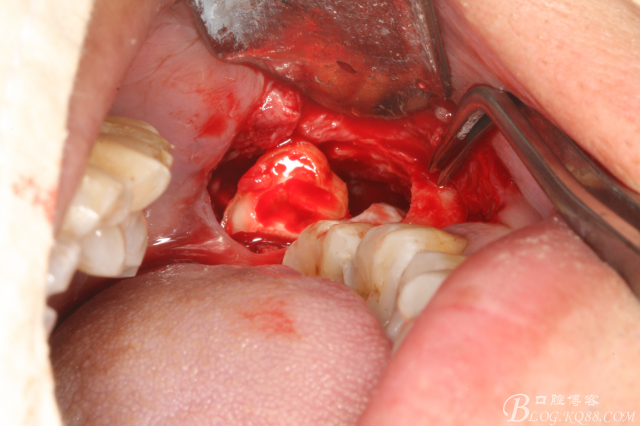

圖三、完全暴露38牙根和牙冠